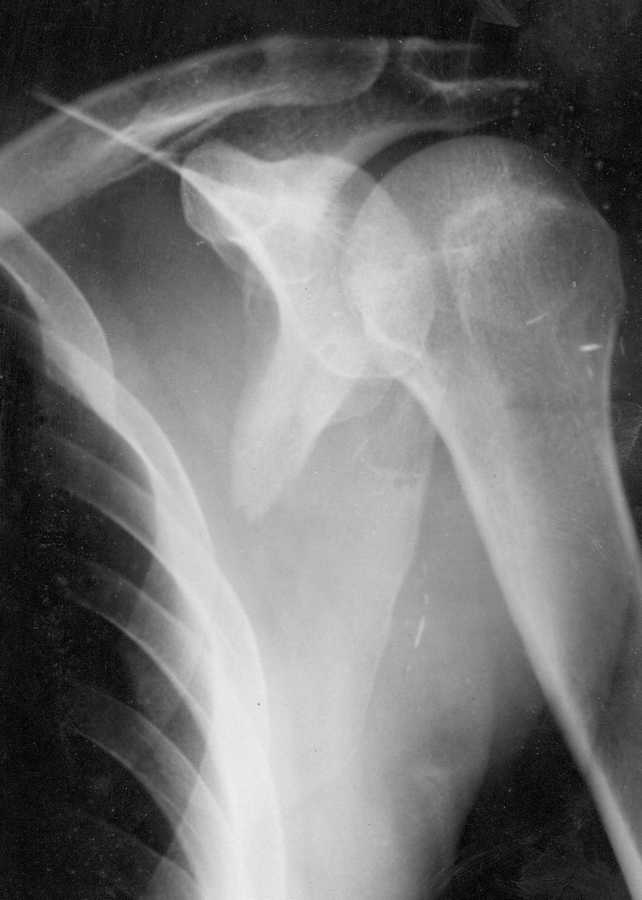

Больной поступил 12.05.09 после избиения битой.При осмотре отёчность в области ости правой лопатки, костная крепитация.

На рентгенограмме перелом латерального края правой лопатки с таким смещением. На других рентгенограммах перелом обеих малоберцовых костей и левой локтевой кости без смещения, множественные ушибы тела. В 2006 году ЧМТ, наблюдается у невролога и психиатра. Находился в РАО. Пока ведётся консервативно на отводящей шины без вытяжения. Какой метод лечения и почему для больного применить?